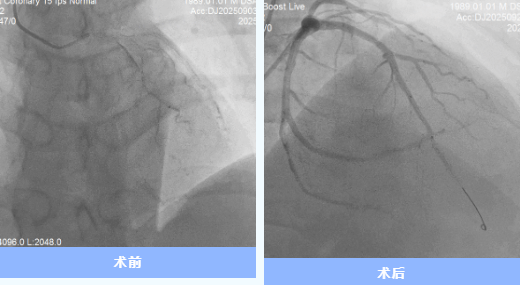

9月29日世界心臟日,35歲的代先生從隨州市中心醫(yī)院康復(fù)出院,將錦旗交予醫(yī)護(hù)人員手中。這背后,是一場由多學(xué)科協(xié)作的20余天的“生命保衛(wèi)戰(zhàn)”。 01雷霆救治:與死神競速 9月3日17時,代先生因“胸痛不適1天,加重1 ...